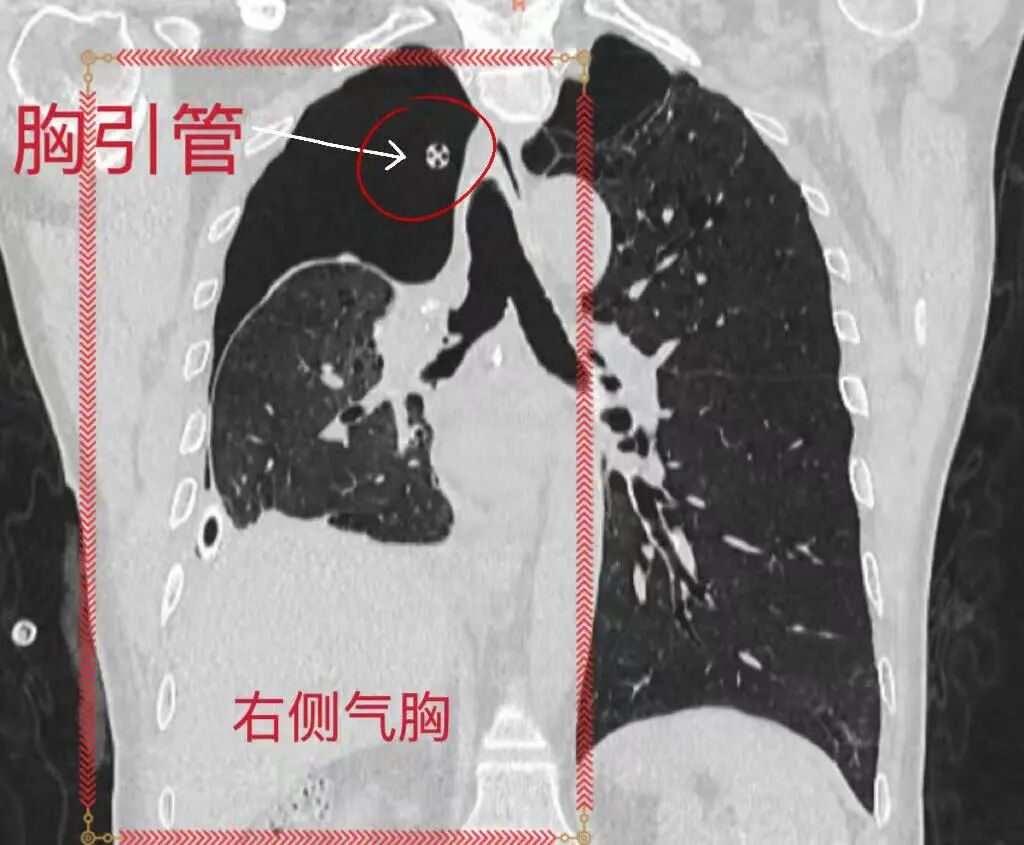

在科室副主任(主持工作)韩睿副主任医师的指导下,李江华副主任医师带领团队首先尝试经胸引管注入亚甲蓝进行瘘口定位,支气管镜下未能清晰显现。随即调整诊疗策略,采用多枚封堵球囊对右侧各级支气管分步封堵、逐一排查,最终明确瘘口并非位于手术支气管残端,而是累及右中叶、右下叶共5个亚段的复杂支气管胸膜瘘。

BPF封堵前右侧气胸持续引流